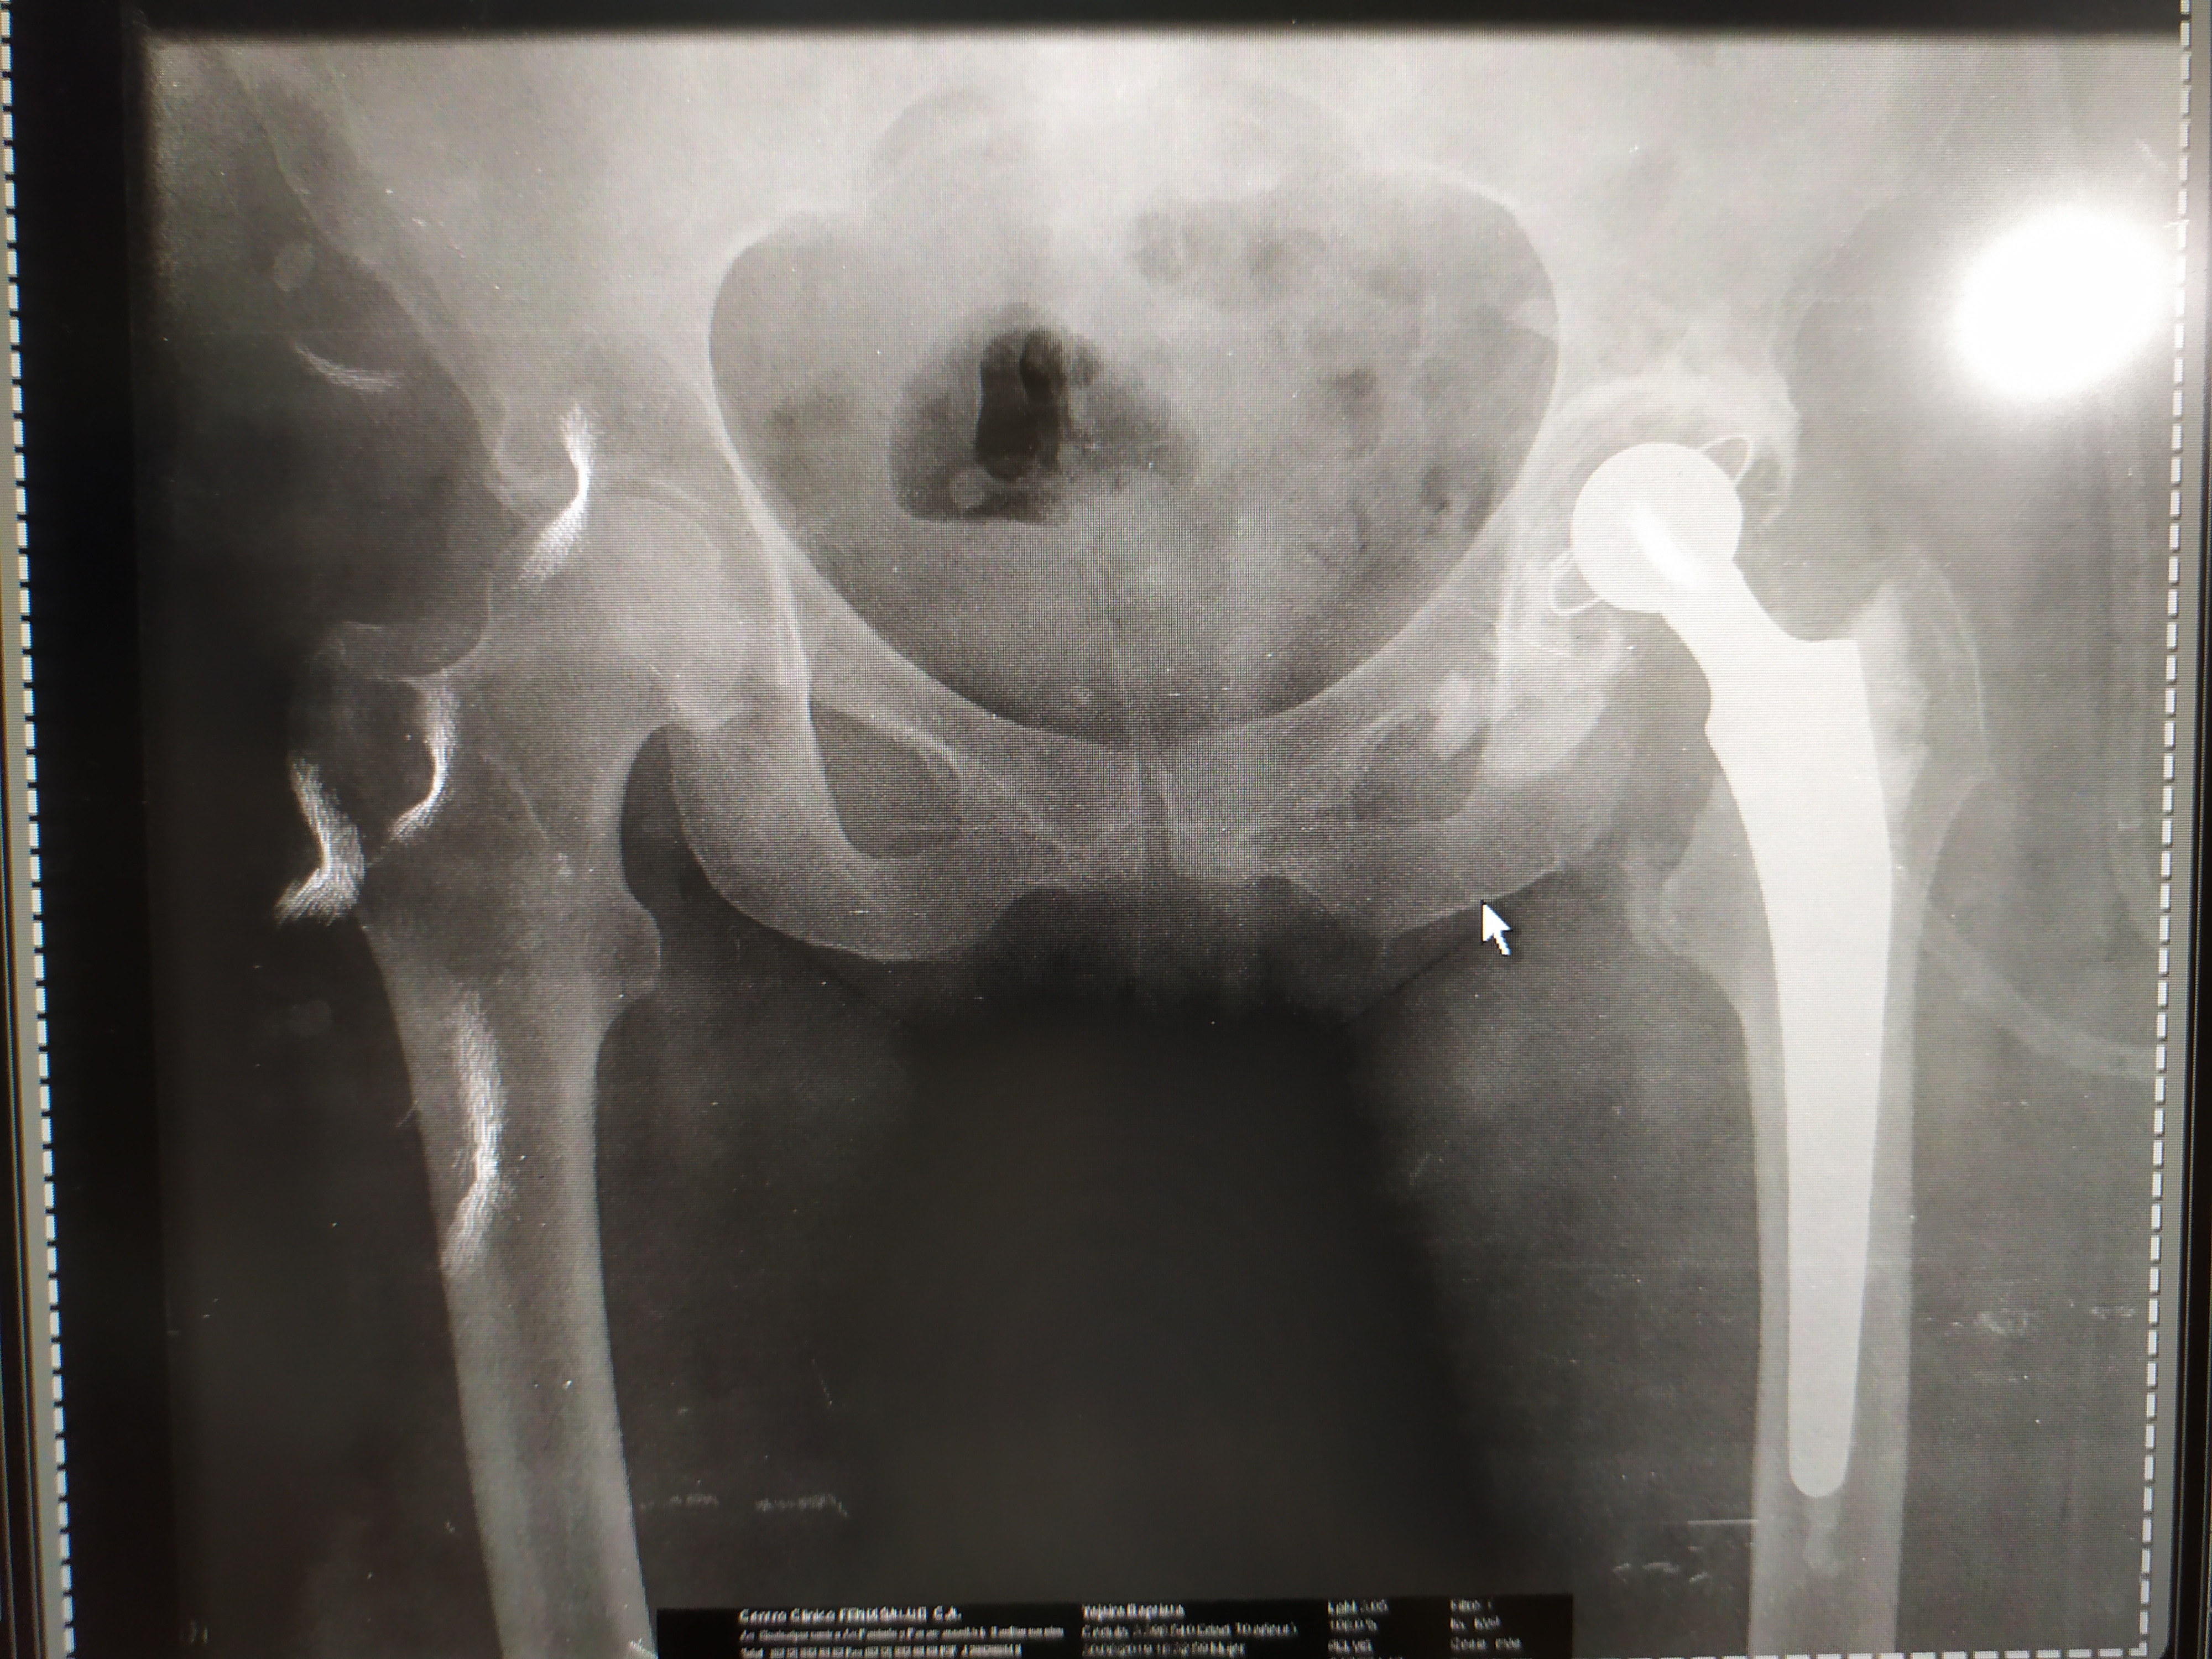

Avascular necrosis in the Hip

Avascular necrosis is the death of bone tissue due to lack of blood supply. Also called "osteonecrosis," it can cause small fractures in the bone and, over time, the collapse of the bone.